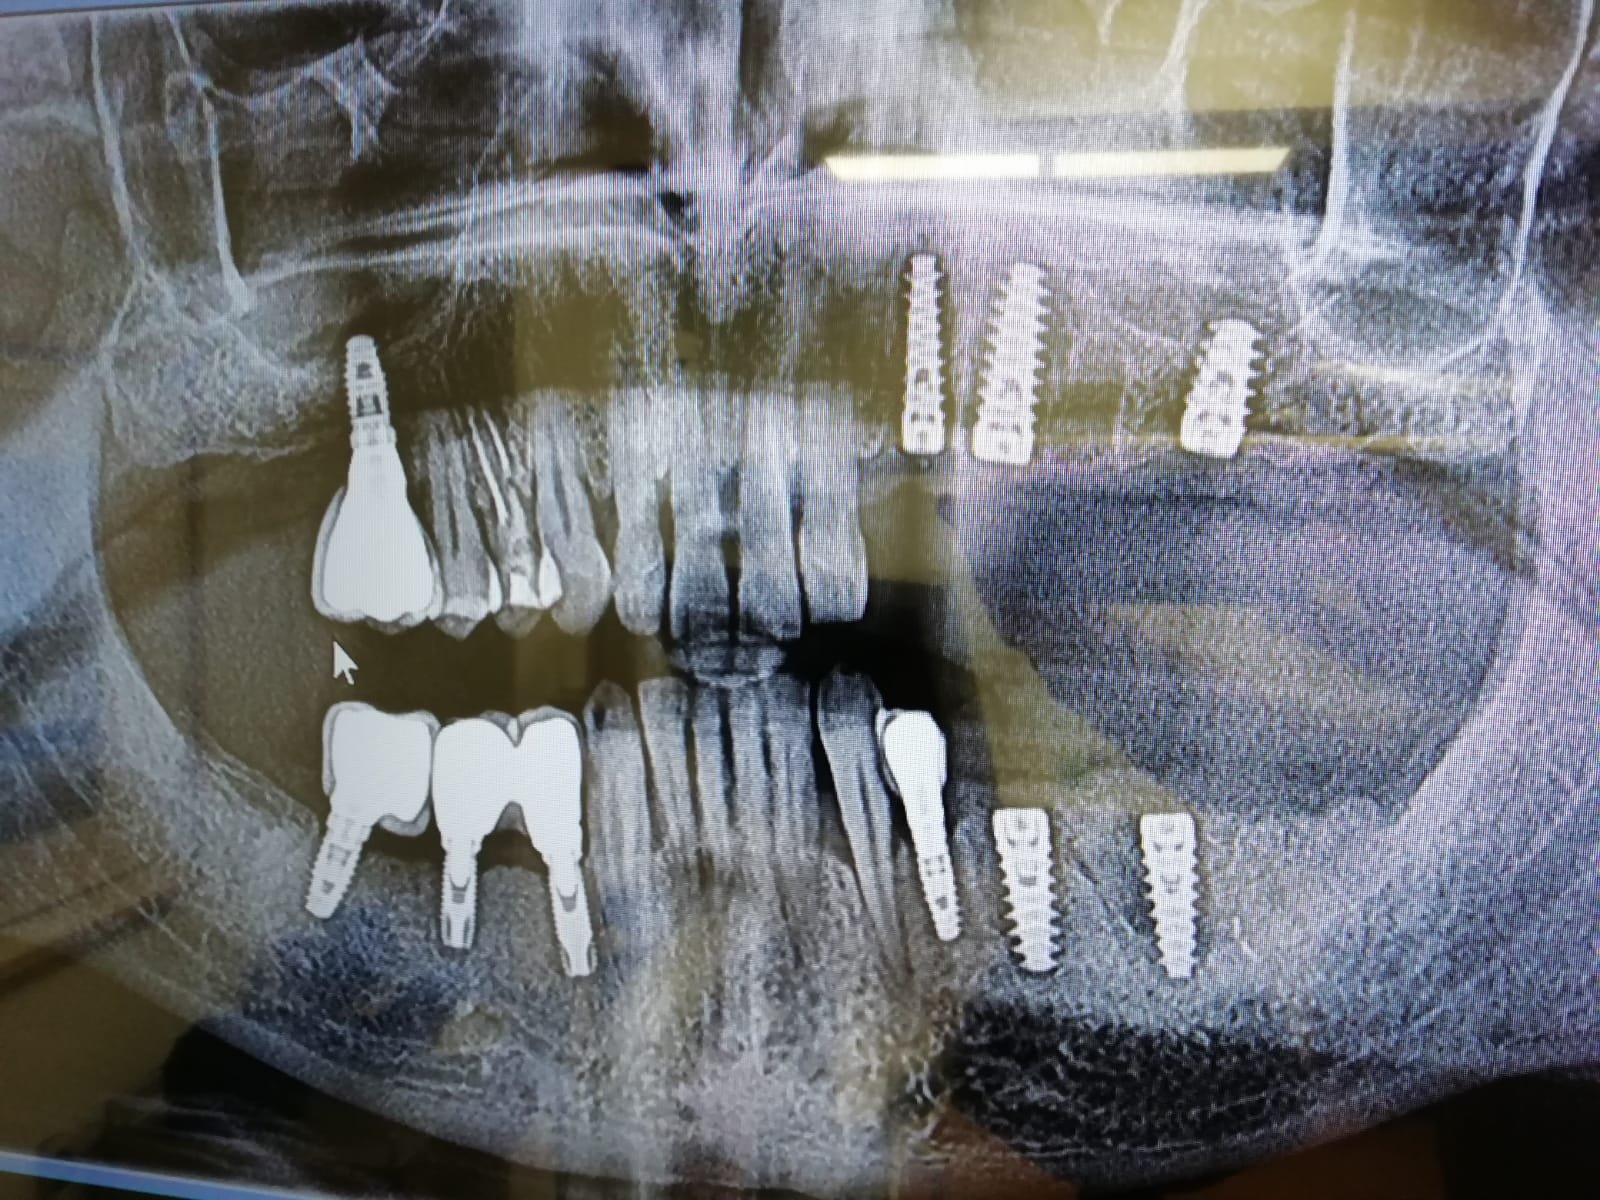

Implantes valencia 1

Necesito saber que marca de implantes son los dos de la derecha. Gracias